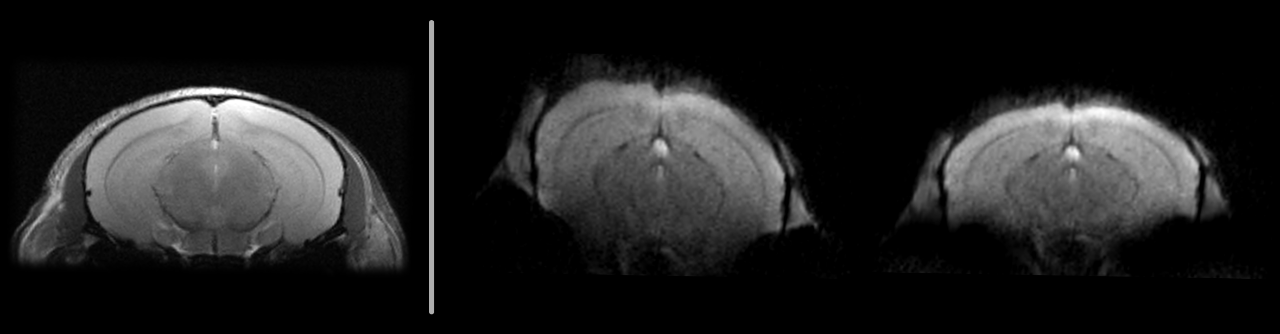

EPIのB0歪み補正

• ロバストなフィールドマップに基づく幾何学的歪みの補正

• fMRIやDTIなどの主要なアプリケーションにおける解剖学的精度の向上

• 標準的な再構成パイプラインへの統合

7Tにおけるin vivoマウス脳のシングルショットEPI:オリジナル(中央)とフィールドマップベースで補正したもの(右)。解剖学的RARE参照(左)。